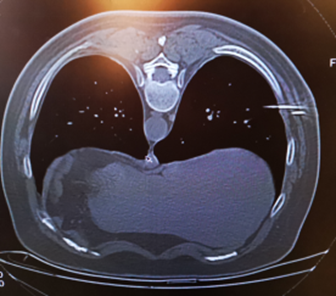

本例患者小结节位于右肺下叶外侧段,正常呼吸情况下,肺脏下界活动度达6-8cm,给定位增加了难度,肿瘤医院综合二A科具有丰富的穿刺活检临床经验,在吴登斌院长悉心指导下,决定采取双针定位技术进行本例肺小结节的术前定位矛的植入,手术过程顺利,无出血及气胸等症状。

△术前定位,设计第一针(固定肺脏)针道

△双针定位技术,插入小结节定位针